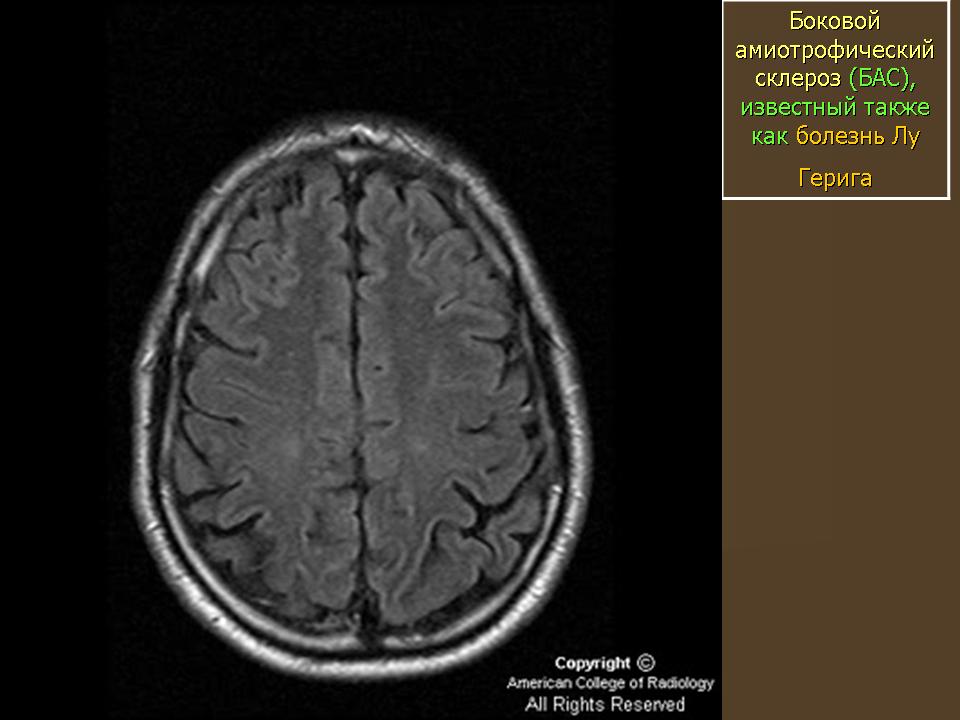

Официальное название заболевания - боковой ами-отрофический склероз (БАС), однако в США оно больше известно под названием «болезнь Лу Герига». Это прогрессирующее нейродегенеративное расстройство было диагностировано в 1939 г. у легендарного американского бейсболиста с таким именем, полевого игрока команды «Нью-Йорк Ян-киз», прожившего после появления первых симптомов всего два года. БАС начинается с повреждения нервных клеток, идущих от головного и спинного мозга к мышцам всех органов и тканей. Когда так называемые двигательные нейроны погибают, головной мозг оказывается не в состоянии управлять работой мышц, и наступает полный паралич.

Представление о том, что такое боковой амиотрофический склероз, дает само название болезни. «Амиотрофический» состоит из трех греческих слов. «А» - отрицание, «мио» - относящийся к мышцам, «трофика» - питание. Таким образом, мышцы у больных БАС испытывают дефицит питательных веществ, а потому атрофируются. Слово «боковой» указывает на область спинного мозга, в которой располагаются погибшие участки нервных клеток. С дегенерацией данной области происходит ее уплотнение («склероз» как раз и означает «затвердевание»). Возможно, самой ужасной особенностью заболевания является то, что больной не утрачивает умственны-ех способностей и осознает все, что с ним происходит.

Наиболее распространена спорадическая форма БАС. Кажется, что болезнь может настичь кого угодно и в любое время. Наследственная форма встречается лишь у 5-10% больных. Ранние проявления заболевания у разных пациентов могут быть неодинаковы, но обычно все начинается со слабости в руках и ногах, речевых расстройств, мышечных судорог, ограниченности движений. Как только затрагиваются дыхательные мышцы, больного помещают в стационар и переводят на искусственную вентиляцию легких.

При БАС поражаются только двигательные нейроны, а чувствительность, слух, вкусовые ощущения и обоняние сохраняются. Однако мотонейроны, ответственные за произвольные движения глаз и мочеиспускание, по неизвестным причинам долгое время остаются ин-тактными. Хокинг, например, до сих пор контролирует сокращение глазных мышц; одно время он использовал для коммуникации брови, поднимая или опуская их в определенных ситуациях. Он может также шевелить двумя пальцами правой руки и использует их для управления синтезатором речи. Администрация по контролю над пищевыми продуктами и лекарственными средствами США (РАО) одобрила применение лишь одного препарата для лечения БАС. Это рилузол, вещество, продлевающее жизнь на несколько месяцев; скорее всего его действие состоит в подавлении образования вредных химических соединений, повреждающих двигательные нейроны.

Что же нам известно о происхождении заболевания? Существует множество гипотез, в их числе - инфекции, влияние наследственных факторов, нарушение работы иммунной системы и химического равновесия в организме, действие токсичных веществ, недостаточное питание. Что именно запускает патологический процесс, остается загадкой. Некоторый прогресс наметился в 1993 г., когда группа генетиков и клиницистов обнаружила ген, ассоциированный с одной из форм наследственного БАС. Он кодирует фермент супероксид-дис-мутазу (8СЮ1), защищающий клетки от свободных радикалов (высоко реакционноспособных веществ, образующихся, в частности, в ходе нормальных метаболических процессов).